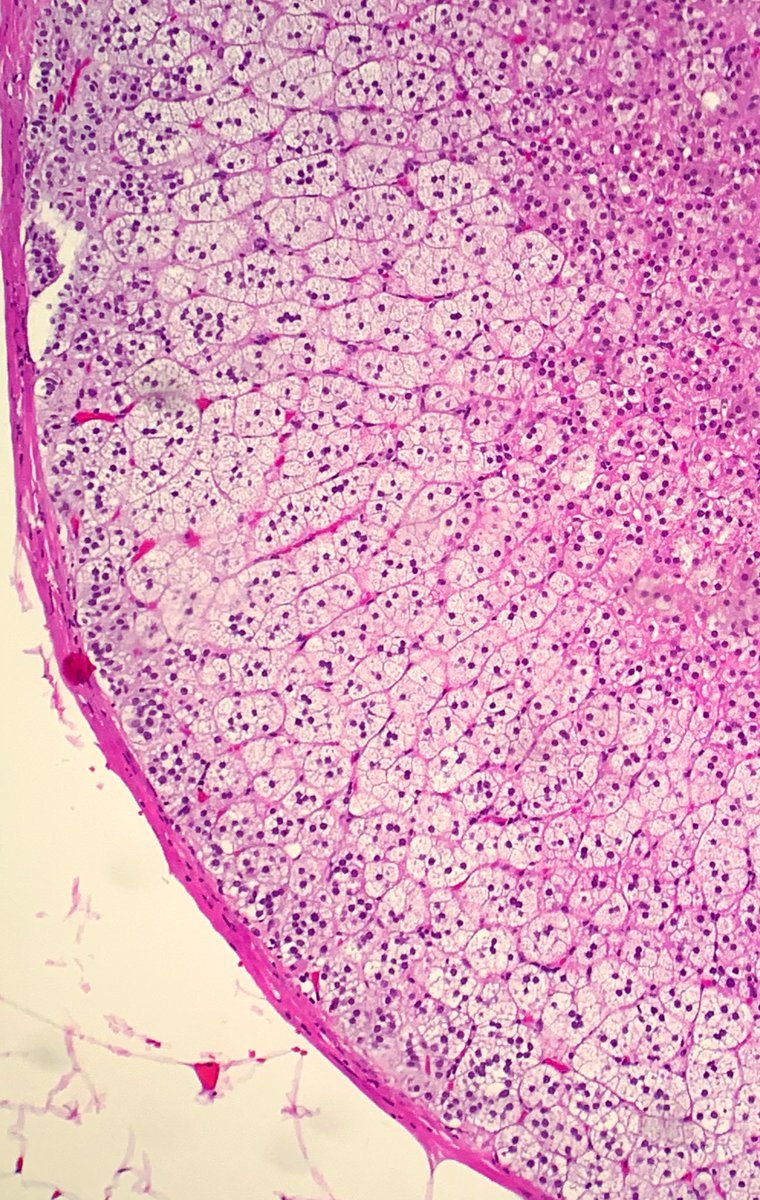

1/4 Dedicated to the memory of Dr Ondrej Hes x.com/GU_Path_Societ… Adult, medullary based kidney tumour - large discohesive polygonal, rhabdoid cells - multinucleated cells - cytoplasmic vacuoles #PathTwitter #PathResidents #Pathology #GUPath Ahmad Dhia GU Pathology Society (GUPS)